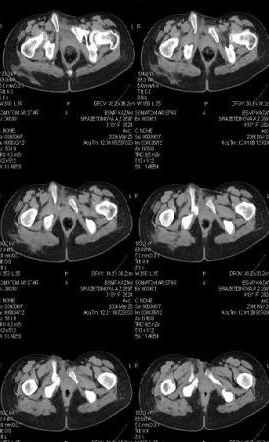

Уважаемые коллеги! Девушка 18л сросшиеся переломы лонных, седалищных костей с обеих сторон, перелом крестца справа,перелом костей голени справа (зио), 3 мес после травмы, АВФ снят с таза.

Патологической подвижности нет. Стоит самостоятельно, ходит с костылями, поскольку 3 месяца практически не ходила. Беспокоит выступание лонной кости в области лобка, хотя объективно грубого косметического дефекта нет. На кт разворот лонной кости в сагиттальную плоскость. Вопрос: стоит ли добиватьсяполной репозиции или же достаточно произвести остеотомию верхушки выступающего отломка?

При более детальном распросе, наверное, удастся обнаружить и другие жалобы, либо они появятся при увеличении нагрузок. Как представляется, задачей лечения будет являться восстановление целостности и стабильности тазового кольца. Оптимальным вариантом может быть низведение левой половины таза, затем реконструкция передних отделов. Варианты выполнения репозиции и фиксации - тема отдельного разговора.

Предоставляю срезы. Если пациентку функционально ничего не беспокоит, стоит ли навязывать ей лечение.